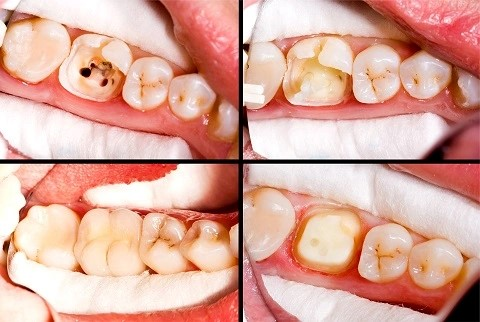

Viêm tủy răng là gì?

- 🔹 Định nghĩa: Viêm tủy răng xảy ra khi vi khuẩn phá vỡ cấu trúc răng và xâm nhập vào tủy.

- 🔹 Phạm vi ảnh hưởng: Bệnh có thể tác động một hoặc nhiều răng trong cung hàm.

Các giai đoạn viêm tủy răng cần lưu ý

- 🔹 Viêm tủy có phục hồi

- Đây là giai đoạn đầu của viêm tủy, thường khó nhận biết do triệu chứng chưa rõ ràng.

- Biểu hiện thường gặp: đau từng cơn, ê buốt nhẹ, kéo dài về đêm hoặc khi ăn đồ quá nóng/lạnh.

- 🔹 Viêm tủy cấp

Đây là giai đoạn viêm tủy tiến triển mạnh, các triệu chứng xuất hiện rõ ràng và dữ dội, ảnh hưởng trực tiếp đến sinh hoạt hằng ngày của người bệnh.

- ⚡ Tủy viêm do lỗ sâu lớn hoặc răng nứt

- Khi vi khuẩn xâm nhập sâu vào tủy qua lỗ sâu hoặc vết nứt, tủy bị kích thích mạnh, áp lực trong tủy tăng, gây đau nhức dữ dội, đau nhói. Cơn đau thường tăng lên khi ăn, nhai, hoặc tiếp xúc thức ăn nóng/lạnh, và không giảm khi dùng thuốc giảm đau thông thường. Đây là lúc bạn cần điều trị tủy chuyên sâu tại nha khoa để loại bỏ vi khuẩn, giảm đau và bảo tồn răng.